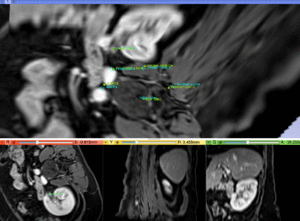

- you should see the newly created transform node in the MRML tree. Locate the MR image and drag its node onto the transform node (release the left mouse button when a box appears around the transform node). The MR image is placed inside the new transform. You should see the views update immediately.

- also drag the "fiducially_MR" node into the transform. Your data hierarchy should look similar to the image on the right.

- use the fade slider to judge the alignment.

- the 3D viewer will be very helpful here to assess the alignment of the fiducial pairs in space.

| MR/CT before registration (click to enlarge) | |

| MR/CT after fiducial rigid alignment (click to enlarge) |